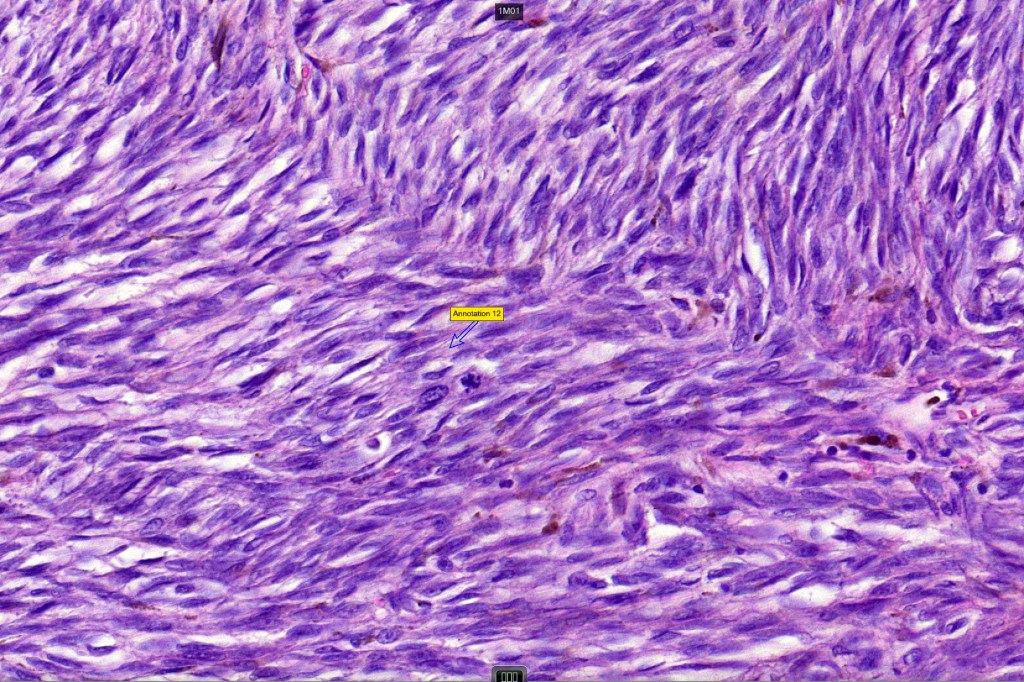

Histological features

•Or melanoma showing admixed blue nevus-like features (dendritic cells and melanophages) in the absence of a precursor lesion

•Nuclear pleomorphism with prominent nucleoli, mitotic activity & abnormal mitoses